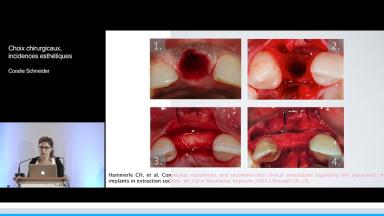

Cette présentation s’intéresse à l’influence des étapes chirurgicales sur le résultat esthétique en implantologie.

Le moment de l’implantation (immédiate, précoce, différée) influe peu sur le résultat esthétique ; l’implantation immédiate ne supprime pas la résorption physiologique post-extractionnelle.

Tous les types d’implants peuvent être utilisés en secteur antérieur, mais l’utilisation de connexions au niveau osseux offre plus de latitude sur le placement de l’implant et sur la réhabilitation prothétique. Afin de limiter les proximités entre implants et entre dents et implants, l’utilisation d’implants de faible diamètre et la réduction du nombre d’implants sont des options à considérer.